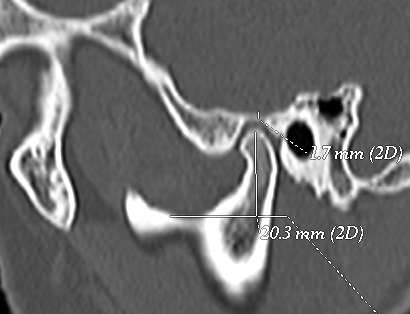

The temporomandibular joint (TMJ) is one of the most complex joints in the body and its harmonious functioning is very important to maintain a normal masticatory system. The morphologic alterations and the asymmetrical position of the TMJ structures may lead the various clinicalsigns & symptoms. Morphology of the temporomandibular joint may be influenced by gender of patients, environmental factor and also food habits at various places. Objective: To evaluate the morphology of the temporomandibular joint using computed tomography, in order to determine the condyle shape, joint space and glenoid fossa roof thickness. Material and Methods: One hundred and six healthy patients (212 TMJs) who visited a private hospital (or the University’s Hospital) for CT brain scan were included to this cross-sectional study sample.The patients were aged between 20–50 years with an average age of 35.46 years. All the images were taken by positioning patients in supine position with 120kvp , 50ma,2.33minute exposure with 0.7mm thick slicesby computed topography machine in all three projection that is Axial, Coronal and Saggital view. Results: For all variables, the mean and standard deviation were calculated, based on gender, and TMJ sides. The Paired t-test was used and P<0.05 will be considered to be significant. Conclusion: Present study showed that thereis positive evidence of temporomandibular joint involvement in elderly patients. Change in morphology and position of condylar head with glenoid fossa and roof thickness are one of the most common cause of degenerative diseases.